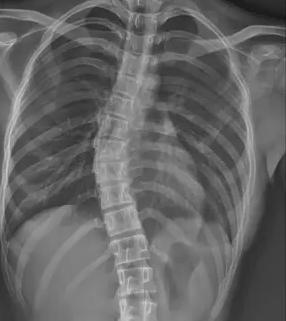

在数字化学习与久坐生活模式普及的当下,青少年脊柱侧弯正以惊人速度蔓延,成为威胁青少年健康的 “沉默流行病”。国家卫健委最新数据显示,我国 10-18 岁青少年脊柱侧弯总体患病率已达 1.2%,2016-2024 年间发病率近乎翻倍。值得关注的是,16-18 岁青少年群体患病率显著高于低龄组,女生患病风险更是男生的 1.6 倍。地域差异同样严峻,西部欠发达地区如甘肃天祝县的疑似病例比例远超上海杨浦区,暴露出医疗资源分布不均的深层矛盾。

当前青少年脊柱侧弯诊疗体系面临系统性困境。在筛查环节,传统 X 线测量 Cobb 角虽为金标准,但辐射风险限制其大规模应用;现有初筛手段假阳性率高达 35%,而低辐射智能筛查技术在基层医院普及率不足 12%,导致大量病例漏诊。疾病管理链条存在显著断层,Cobb 角<10° 的轻症患者因缺乏标准化干预方案,错失黄金矫正期。保守治疗领域,支具治疗依从性不足 40%,定制精度误差超 15%,全国注册矫形师缺口达 83%;物理治疗资源配置失衡,70% 的基层医疗机构尚未建立规范康复训练体系。

针对上述痛点,医疗科技企业与科研机构正联合构建智慧防治体系。迪纳医疗研发的全幅 Dira-DUC 技术,通过 AI 辅助三维重建实现单次 0.02mSv 低剂量成像,较传统设备辐射量降低 87%。其自主研发的脊柱侧弯风险预测模型,整合 120 万例临床数据,可精准识别高危人群,筛查准确率提升至 92%。诊疗环节引入智能 Cobb 角测量算法,将人工测量误差从 ±5° 压缩至 ±1.2°。在支具治疗方面,智能监测支具内置压力传感器与物联网模块,实时反馈佩戴数据并生成个性化调整方案。物理治疗领域,标准化训练课程已纳入国家卫健委基层康复指南,配备 AI 动作捕捉系统的智能训练舱正在全国 127 家县级医院推广。